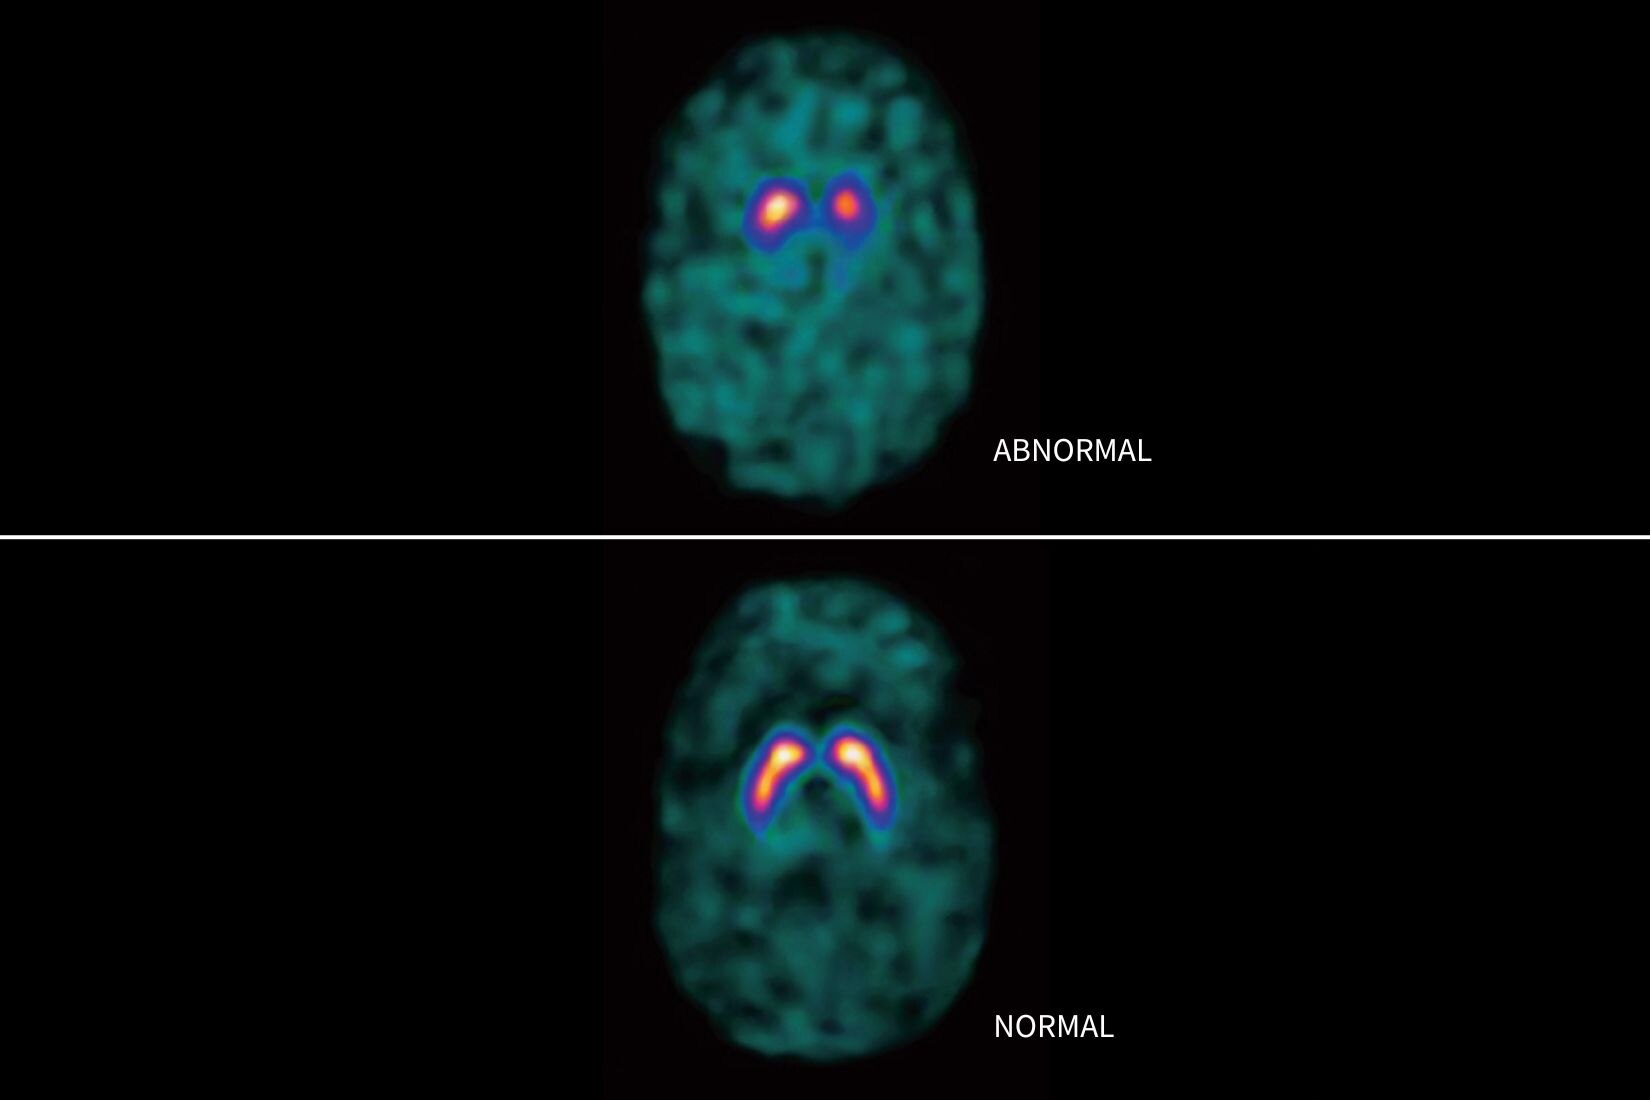

Protocollo per l'ictus cerebrale

• Funzione di registrazione delle immagini per ridurre al minimo gli effetti del movimento del paziente

• Funzione di rimozione delle ossa per eliminare automaticamente il cranio dal set di dati

• Segmentazione dei ventricoli cerebrali con Deep Learning per evitare l'inclusione della materia ventricolare nei risultati quantitativi e migliorare l'ispezione visiva delle mappe

• Selezione automatica dell'input arterioso e dell'output venoso. Se necessario, è possibile regolarli entrambi con facilità.

• Generazione automatizzata di tutte le mappe funzionali: flusso sanguigno, volume ematico, tempo medio di transito e tempo di transito al picco IRF (Tmax)

• Definizione automatica del piano di simmetria da utilizzare per eseguire il mirroring delle ROI e delle relative soglie

• La classificazione dei tessuti consente la visualizzazione di regioni segmentate in base a valori assoluti o relativi, soglie personalizzabili e mappe di input selezionabili dall'utente.

• Il volume e il rapporto di mancata corrispondenza vengono calcolati in base al volume di perfusione modificato e alle ROI con volume di perfusione basso